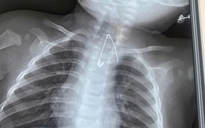

Dị vật mắc kẹt trong cơ thể chị H. suốt 11 năm

Các bác sĩ Bệnh viện Hữu Nghị tiến hành thăm khám, chụp X-quang khung chậu và siêu âm đầu dò âm đạo, kết quả phát hiện một dị vật bằng kim loại kích thước khoảng 15 mm được xác định là một đoạn của kim khâu nằm tại vùng tầng sinh môn của bệnh nhân.